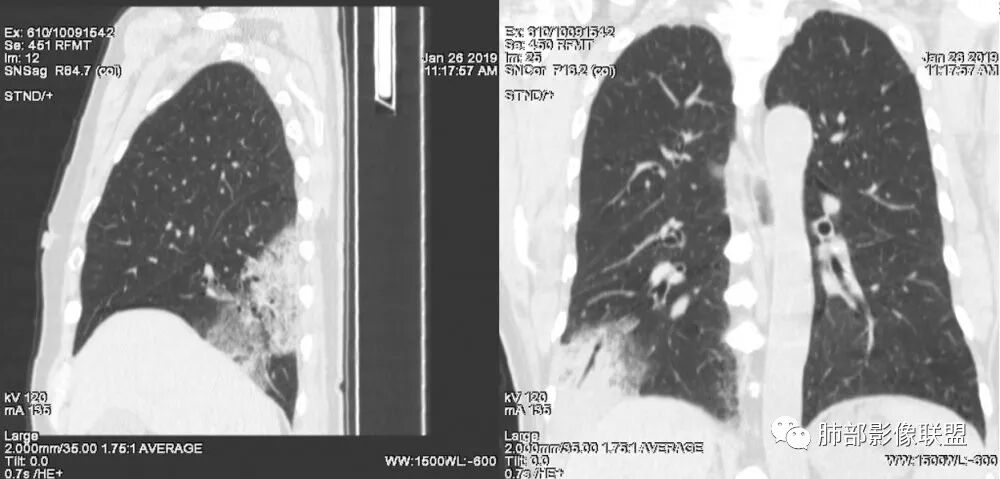

老年女性,右肺下叶沿胸膜下大片状高密度影,外周磨玻璃影,边界较清,内可见蜂窝征及支气管充气征,考虑肺炎型肺癌。

老年女性,咳嗽咳痰病史,右肺下叶大片磨玻璃实变影,胸膜下分布,支气管进入后扩张、僵直,磨玻璃影边界清楚,考虑粘液腺癌。鉴别肺炎。

右肺下叶基底段靠胸膜实变/磨玻璃混杂密度影,边界清楚,内见多发空泡(蜂窝样趋势改变?); 临床:咳嗽咳痰,无发热、胸痛; 考虑腺癌:无发热,感染性病变不首先考虑;部分层面形态类楔形,鉴别肺栓塞

老年女性,右下肺实变影,病灶里有小叶内间质增厚,周围GGo,支气管扩张,粘液性腺癌?淋巴瘤?

中年女性,咳嗽咳痰。右肺下叶片状高密度影,部分实性密度,周围见边界清晰磨玻璃影,内见小空泡,实性区部分支气管堵塞,有重力效应,考虑肺炎型肺癌,建议查痰脱落细胞。

老年人,右肺下叶斑片状阴影,病灶有膨胀性,边缘可见磨玻璃影,其边界清晰,内见僵硬的支气管,部分支气管扩张,首先考虑占位性病变,粘液性腺癌可能。鉴别感染性病变,后者边缘多有收缩性改变或者平直,内部支气管走形自然。

中年女性,右肺下叶沿胸膜下大片状高密度影,实变加GGO,外朝内发展,边界较清,内可见蜂窝征及枯树征,考虑肺炎型肺癌。

右肺病灶,病灶较大,实性+周边ggo,边界清晰,胸膜下分布,长轴平行于胸膜,内部支气管充气征,因不发热,暂不考虑感染性病变,支持肺炎型肺癌。

女性,咳嗽咳痰不发烧,右下外基底段实变影,边缘清楚GGO,有充气支气管征,枯树枝不明显,由外向内;诊断:肺炎型肺腺癌;鉴别:1、肺栓塞(外型神似,但无胸痛丶咯血);2丶肺炎

老年女性,右下肺实变影,糊墙,外朝内发展,病灶里有小叶内间质增厚,周围边界清楚了GGO,支气管扩张明显,考虑粘液癌;不符合点,支气管扩张太厉害了,鉴别淋巴瘤。

患者中年女性,咳嗽咳痰就诊。胸部CT:右肺下叶后基底段片状实变影,由胸膜向内发展呈扇形,病灶里有小叶内间质增厚、蜂窝状影,周围边界清楚GGO,内可见扩张支气管,淋巴结无明显肿大。综合符合粘液腺癌。

老年女性;右下肺混合实变影,呈楔形改变,边缘清晰,支气管进入且扩张,蜂窝状改变,考虑粘膜相关淋巴瘤,鉴别粘液腺癌,肺栓塞。

女,55咳嗽咳痰,右肺下叶片状实变,磨玻璃影及蜂窝影,考虑粘液腺癌。

老年女性,咳嗽、咳痰。右肺下叶沿胸膜下大片状高密度影,外周磨玻璃影,边界较清,小空泡,蜂窝征及支气管充气征,叶间裂串珠征,考虑:肺炎型肺癌,鉴别:肺克,链球菌,NTM等感染。

右肺下叶大片状影,密度不均匀,部分实变部分磨玻璃,大部分病灶尚清晰,其内支气管稍扩张,中年女性,首先考虑粘液腺癌,待鉴别淋巴瘤,常规抗炎治疗后复查。

中年女性,右肺下叶实变,近似扇形,外朝内发展趋势,外围紧贴胸膜面,中心密度略高,边缘密度略低,病灶内支气管略扩张。考虑肺炎型肺癌。常规建议抗炎治疗后复查,如无变化或变化不明显,建议穿刺活检。

胸膜下,实变,毛玻璃影,囊,边界清,枯枝,粘液腺。

老年女性,右肺下叶大片实变,小叶间隔及小叶内间隔增厚,边界较清,其内支气管似乎可见稍扭曲,分支减少。考虑1.肺炎型肺癌2.结合临床除外类脂性肺炎。

起源于胸膜下,实性成分,边缘Ggo,边界清晰,内可见小叶间隔增厚,粘液腺癌可能。建议先消炎后复查。

右肺下叶胸膜下大片状MGGO,其内结构紊乱,可见空泡征,病灶内近端支气管扩张,远端闭塞,形态不规则,边界部分清楚,部分似清非清,考虑粘液腺癌,鉴别淋巴瘤

该病灶主病灶位于胸膜下(肋膈角处),边缘膨隆改变,周围毛玻璃,边界清楚,病灶内支气管僵直,轻度扩张,小分支无,符合枯树枝改变,有多发小空泡(难与支气管区别),应该符合肺炎性肺癌,但无蜂窝,没有增强无法判断有无粘液、血管特点,如果周围显示的空泡是支气管,其已达到远端,这些有符合炎性特点,工作中,我会先抗炎膨后复查再定。

这是潘老师说的外向内吗?右下实变,蜂窝,GGO,支气管变形迂曲,局部膨胀感,肺炎性肺癌,粘液腺癌可能。常规先抗炎再复查。鉴别淋巴瘤,淋巴瘤支气管一般不变形,壁光整,病程长。

1.本例病灶较大片混杂密度影,胸膜下分布为主(未沿着支气管分布),该分布特点可见于大叶性肺炎、干酪性肺炎、淋巴瘤及粘液腺癌等。可惜未提供增强扫描图像。

2.病灶示中央实变区,周围GGO,可见明显小叶间隔增厚,GGO边界清楚,应当考虑到恶性病变的可能性。肺炎因炎性水肿及渗出,影像上边界常模糊不清,注意早期粘液腺癌可出现似清非清的边界。粘液腺癌因粘液成份较多,密度一般偏低,纵隔窗病灶常会消隐或范围会明显缩小,这不同于炎性实变。

3.病灶内支气管走形略显僵直,侧支少(粘液阻塞),也符合肺腺癌的枯树枝征。而大叶性肺炎的支气管是管壁光整、通畅、自然,结核的支气管常常壁增厚,甚至狭窄后扩张;

4.患者临床症状不重,临床炎性指标不高,结合肺内影像,应警惕肺炎型肺癌。